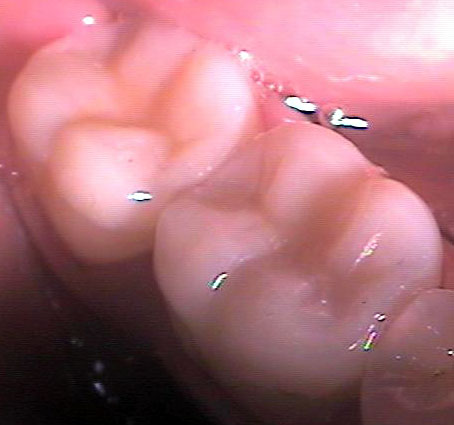

На снимката вляво - долен втори молар с циментирана композитна вставка (случай на

д-р Явор Симеонов). Вижда се запазена стена от зъба в горната част на

снимката. Възстановяването е заснето 20 месеца след поставяне върху

зъба, налице е отлична адаптация и пълна липса на вторичен кариес или

каквото и да било оцветяване по границите композит/твърди зъбни тъкани.

В случая не се наблюдава загуба на блясъка на композита - нещо, което не

винаги е налице, както посочихме по-горе. Какво бихме могли да кажем в

заключение? Композитната вставка е може би оптималното съотношение

цена/качество за възстановяване на зъб с голям кариозен дефект.

Същевременно за нейната изработка не се изисква отнемане на голямо

количество здрави зъбни тъкани, както е при обвивната корона.

Подготовката на зъба, снемането на отпечатък и циментирането на вече

готовата вставка отнемат по-малко клинично време в сравнение с

изработката на пломба; недостатък обаче е необходимостта от повторно

посещение в кабинета. Все пак сумарно двете посещения почти винаги като

време отнемат по-малко от времето за изработка на конвенционална пломба.

Това е от значение за пациенти, които не обичат да прекарват много време

на стоматологичния стол. Налице е и друго значително предимство на композитните пред

керамичните вставки - възможността за извършване на многократни корекции във

всяко едно отношение. При поява на пукнатини между вставката и зъба е възможно

да се извършват наслагвания на композитен материал; също така са възможни

корекции във формата и цвета на възстановяването, тъй като композитите за

клинично приложение са тотално съвместими и осигуряват химична връзка с

лабораторните композити. Това предимство следва да се има предвид при съзъбия с

повишена склонност към развитие на кариес - дори и след години при развитие на

кариозен дефект в съседен участък могат да се извършват наслагвания и репаратури

във всякакъв обем без цялостна подмяна на вставката.